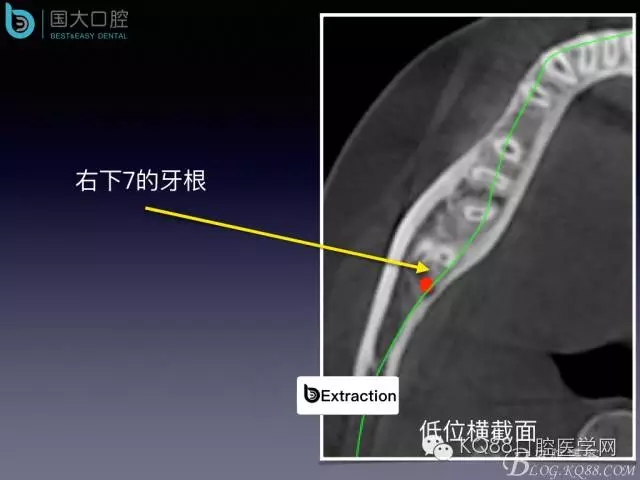

阻生牙的預(yù)防性拔除

- 牙齒拔除適應(yīng)證及第二磨牙遠中齲病